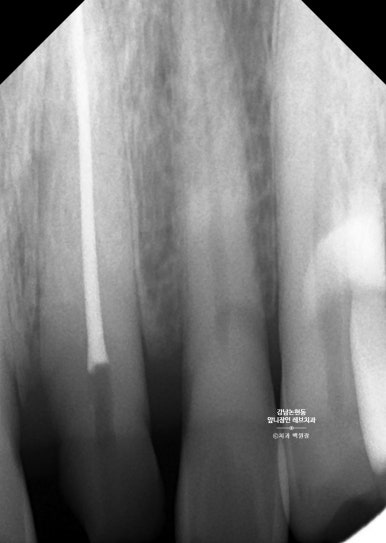

신경치료를 잘 마무리하고나서 앞니를 찍어보았습니다.

세상 가장 어려운 치료 중 하나인

가운데 앞니 크라운 1개 만들기.

거의 무에서 유를 창조한 셈인데요.. 저 남아있는 치아 안에 굵직한 기둥이 심겨져 있습니다.

잘 보시면 뿌리쪽에 약간 어두운 치아가 있는데, 그것이 본래 갖고 계신 자기 치아이고,

보다 밝은 색으로 대부분을 이루고 있는 부분이 기둥 (fiber post) + 레진 코어 (resin core) 입니다.